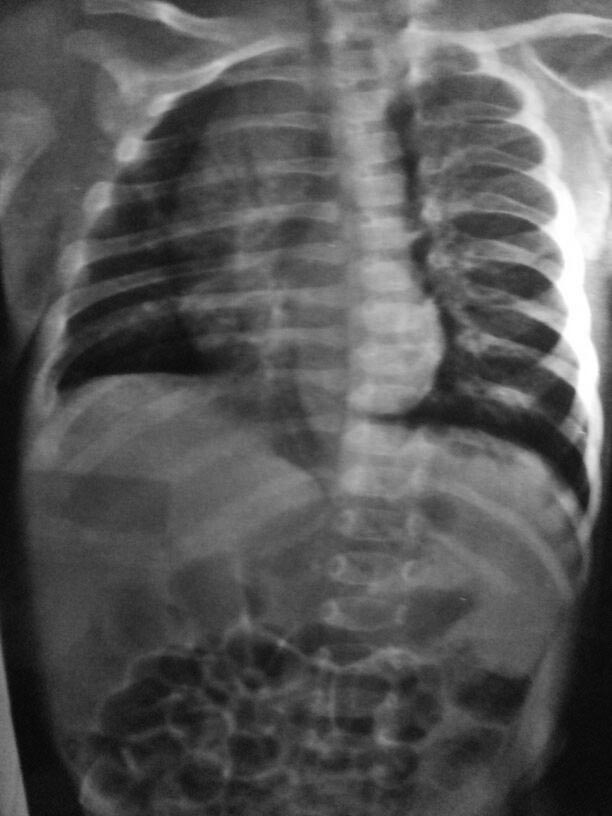

Здравствуйте уважаемые коллеги. Ребенок возраст 45 дней, поставлен диагноз врожденный сколиоз первой ст.

Прошу.., кто сталкивался с такими пациентами., помочь в тактике лечения.